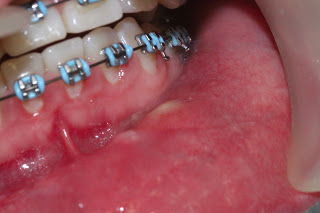

La paciente se presentó con dolor leve (2/10 en la escala análoga del dolor), ligera inflamación en el hemilabio inferior izquierdo y drenaje de material purulento (Figura 1).